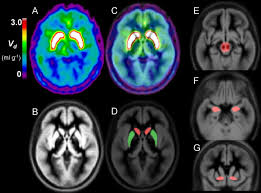

An F-DOPA PET scan is a specialized imaging test designed to study dopamine activity in the brain. It plays a crucial role in diagnosing conditions such as Parkinson’s disease, movement disorders, certain neuroendocrine tumors, and complex neurological symptoms. The reason many people look for Affordable F-DOPA PET Scan Services is because the tracer used—called F-18 DOPA—is highly specialized, and the process requires advanced nuclear medicine technology.